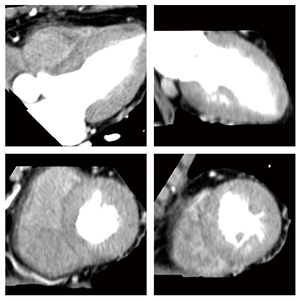

●症例1:Normal case

57歳,女性。負荷Dynamic CTPでは全体に心筋の信号が均一で非常に安定している(図1)。また,Definition Flashのコンソールに搭載されたソフトウェア“syngo Volume Perfusion”により,5分程度の解析でVoxel-wise MBF mapを作成することができる。これをCTAとフュージョンすることで冠動脈の支配域と,その血流状態が明瞭に把握可能であり,正常例では外膜側と比べると内膜側に向かってグラディエントのついた心筋血流値となっているのがわかる(図2)。遅延造影CTでも,全体に均一なCT値が得られている(図3)。

図1 症例1:負荷Dynamic CTP |